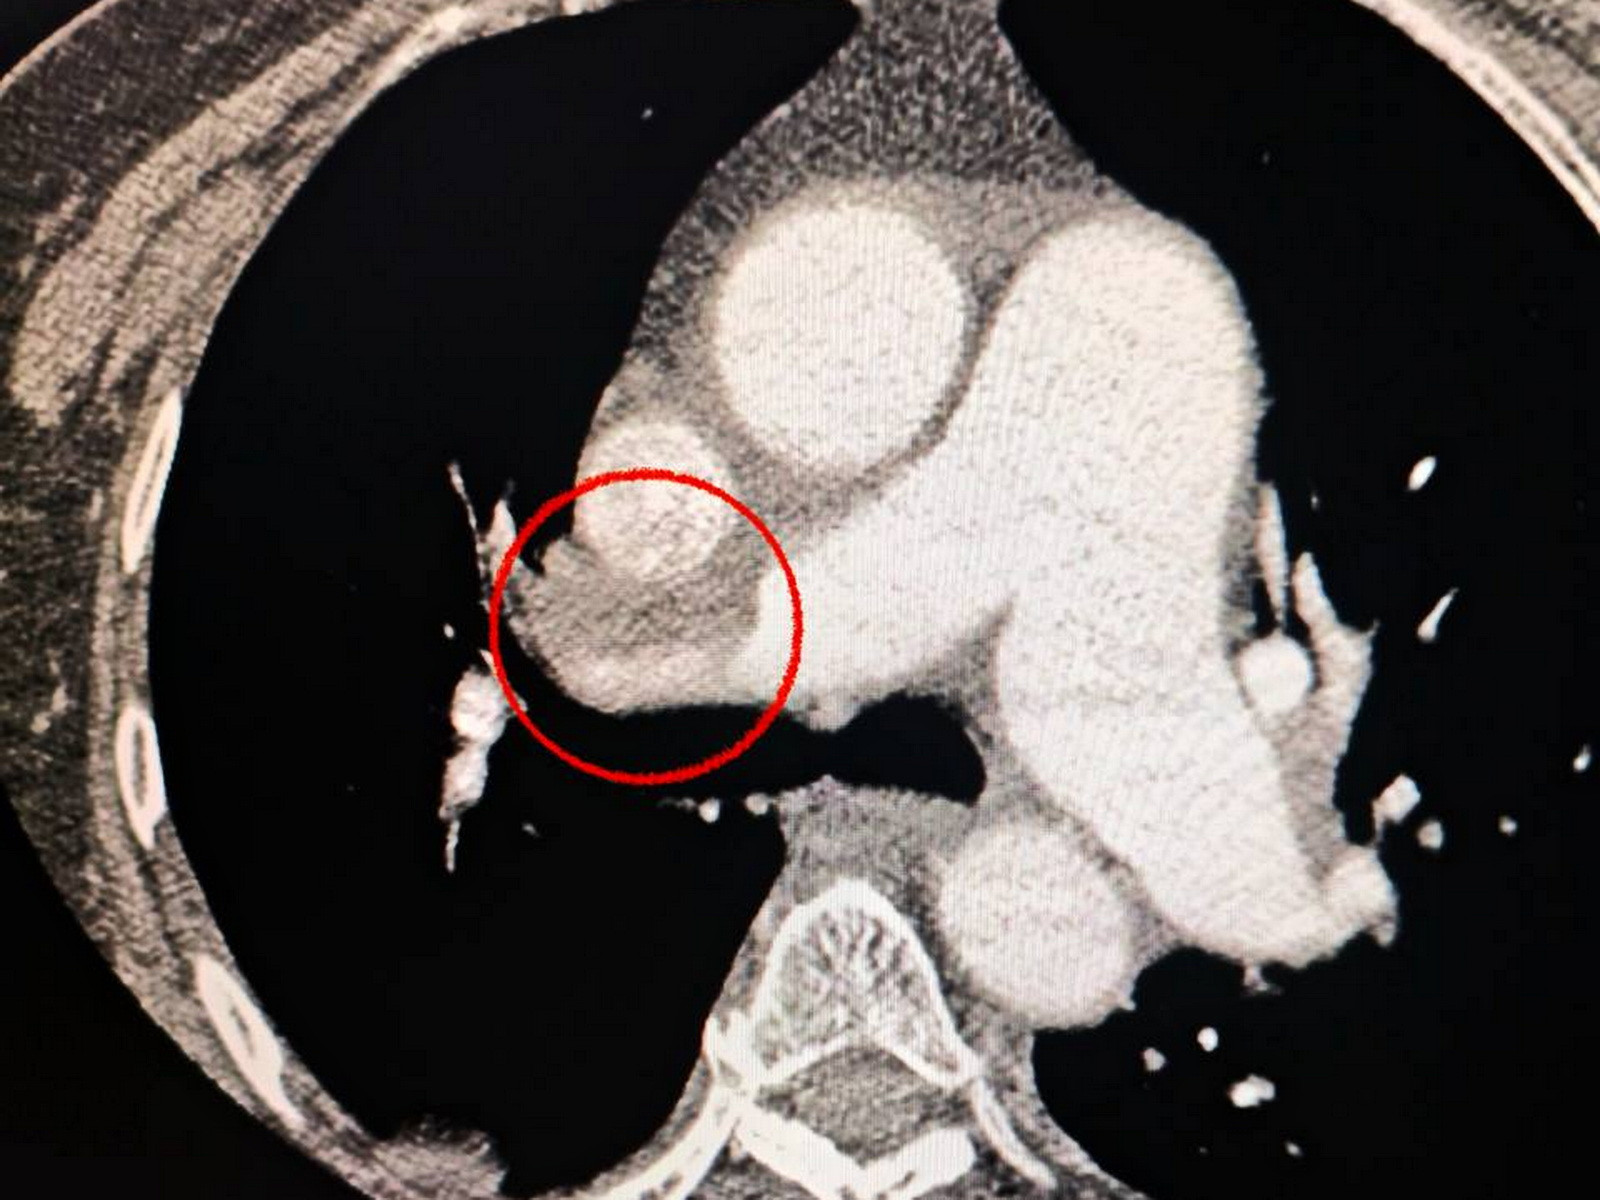

Одеситка потрапила до медзакладу з важким гострим мозковим інсультом, а під час обстеження на комп’ютерному томографі лікарі виявили закриття середньої мозкової артерії. Медики також зафіксували, що пацієнтці важко дихати, тому додатково обстежили легені і встановили тромбоемболію легеневої артерії.

Мультидисциплінарна команда лікарів ухвалила рішення провести одночасну тромбоектомію з мозкової та легеневої артерій. Операція пройшла успішно, наразі пацієнтка почувається значно краще, вона перебуває при свідомості та вже рухає кінцівками.